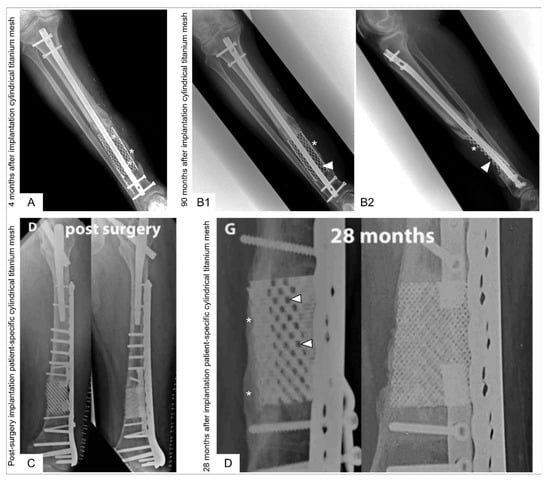

Further reports followed on the use of modified spine titanium mesh cages with allograft [22,124,125,126] as well as the combination of cylindrical titanium mesh cages with ABG [126,127] or ABG supplemented with rhBMP-2 [128]. Following these case reports, major trauma centres worldwide began to apply cylindrical titanium mesh implants either as the previously described cylindrical (spinal) titanium mesh cage (DePuy-Synthes, Warsaw, Indiana) as reported in 17 patients by Attias et al. [126] or as a cylindrical 3D additive manufactured titanium mesh cages as reported in 19 patients by Pobloth et al. [129]. Attias et al. [126] implanted the non-patient-specific cylindrical titanium mesh cages (mean length 8.3 cm, range 2.6 to 13 cm) as an adjunct to either an intramedullary nail or plates and filled with allograft (13/17), Reamer-Irrigator-Aspirator (RIA) system graft material (2/17), and combination RIA system graft material/allograft (2/17). Device failure was observed in two patients (12%), and four patients (24%) had a residual limb-length discrepancy of a mean 1.5 cm (range 1 to 3 cm). Pobloth et al. [129] implanted patient-specific cylindrical 3D additive manufactured (selective laser sintering, SLS) titanium mesh cages (DePuy Synthes) augmented with either RIA system graft material or stuffed with a fibula transfer [129]. The authors report on two representative patients in detail while it was stated that “not all patient cases showed consistent bone defect bridging” [129]. Bony integration at the implant–bone interface was observed in the two detailed case descriptions, but no evidence of bone formation throughout the titanium mesh implant 28 months (case 1) and 8 months (case 2) after implantation [129] was observed. Challenges associated with cylindrical titanium mesh cages are depicted in Figure 5.